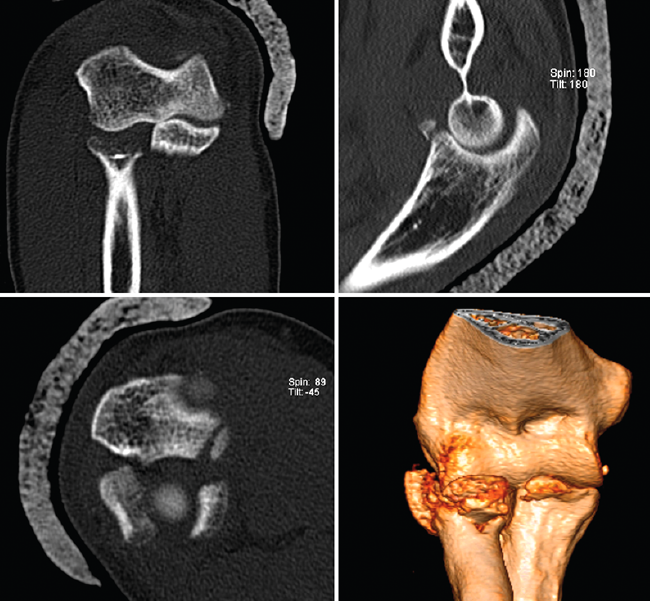

Tomografía computarizada

La tomografía computarizada (TC) –y las reconstrucciones TC-3D– es una exploración complementaria de gran utilidad en los casos de inestabilidad de codo, sobre todo en aquellos en los que se sospeche la presencia de fracturas asociadas.

La mejor exploración complementaria para evaluar las fracturas de coronoides es el estudio de TC, que además de permitirnos clasificar la fractura de coronoides por su tamaño (clasificación de Regan y Morrey)(27), nos permitirá valorar la fractura en un plano coronal (clasificación de O’Driscoll et al.)(28) (Tabla 3). Cuando el aspecto anteromedial de la coronoides está afectado, en la TC, también podrá apreciarse la inestabilidad rotatoria del codo.

Fractura-luxación transolecraneana

Esta lesión se encuentra dentro del espectro de las lesiones de la inestabilidad compleja de codo, aunque existen diferentes estudios donde se ha reportado la ausencia de lesión discernible en los estabilizadores ligamentosos(34,35,36). Esto comporta que el principio fundamental del tratamiento de estas lesiones es restablecer la anatomía de la fosa sigmoidea mayor y la coronoides. Restablecer la estabilidad del principal estabilizador del codo (articulación ulnohumeral) es suficiente para restablecer la estabilidad del codo (Figura 16).

Figura 14. Tríada terrible de codo derecho donde puede apreciarse en las imágenes de tomografía computarizada la fractura de la cabeza del radio, la fractura de la coronoides y la subluxación posterolateral de la ulnohumeral.